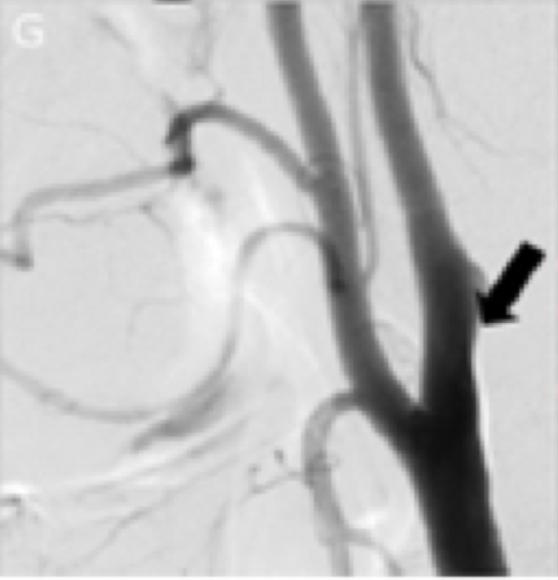

4周后患者拟进一步行颈动脉支架置入术。然而,术中进行的诊断性血管造影显示:颈动脉夹层几乎完全消失,未见明显的官腔狭窄以及内膜瓣(图1G)。右侧颈动脉球水平可见呈喙状的一个微小突起(图1G),可能是此前夹层的残留。因此,该患者最终未行支架置入。三维旋转血管造影显示AMCA双支完全再通(图1H)。3个月后随访,该患者的改良Rankin评分为0分。